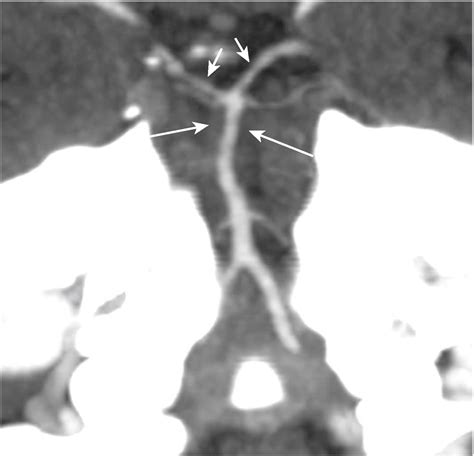

Post-Dural Puncture Headache

Post-dural puncture headache (PDPH) is a specific type of headache that can occur after a spinal tap or epidural. It is caused by a leak of cerebrospinal fluid (CSF) from the puncture site. PDPH typically occurs within a few days after the procedure and can be quite debilitating. Symptoms of PDPH include:

• Epidural Blood Patch: A procedure where a small amount of your own blood is injected into the epidural space to seal the puncture site and relieve the headache.